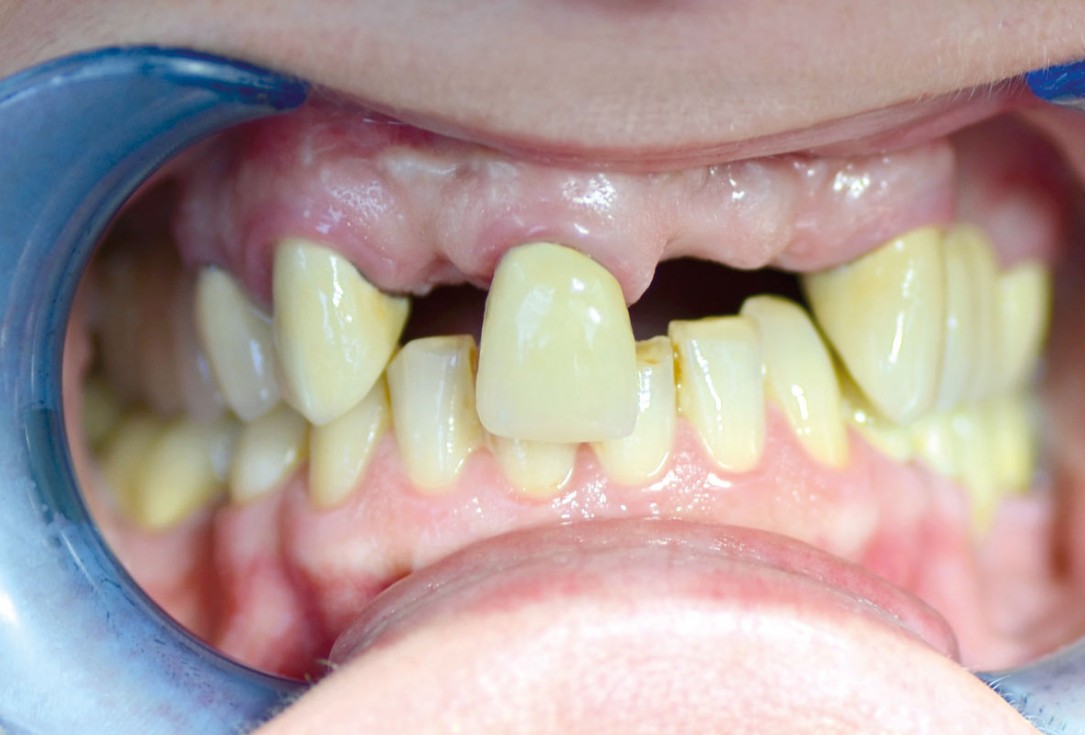

Initial situation: missing teeth #11 & 12 and badly broken #21 root